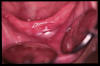

CM Hiperplasia por prótesis